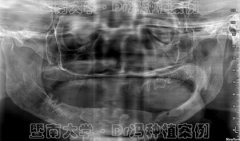

童心不老!花甲长者种一口好牙 欲再次“横渡珠

1年换4副假牙的书法家1天“长”新牙 专家解读这

一年换了4副假牙,都抵不上5颗种植牙!七旬书法家曾令校14年前就开始掉牙,活...【详细】

【现代健康网】50出头牙齿几乎全掉光?大部分人

正常的情况下,每个人会拥有28~32颗恒牙,很多人认为,缺一两颗牙无所谓。事实...【详细】